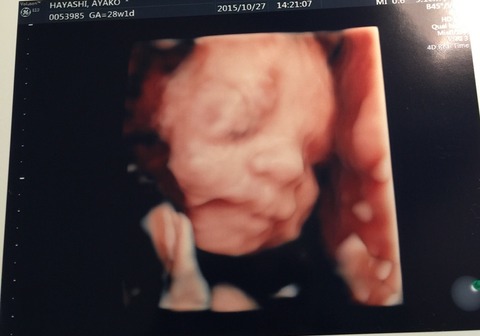

…って事で、昨日は撮影後に4Dエコーなるものを見る為に妻と病院へ。

タイミング次第では、全く顔が見えない事もあるそうで我が子の顔が見れるのか?少しドキドキしてたんですが…

無事?ご対面出来ました(^ ^)

結構動いてたので手足が邪魔して見えなくなったりしましたが…

手も足も元気な証拠かな?とか思いつつ、右手の指がなんとなく5本確認できたのでハサミは握れるな!とかも密かに思ったりしてました( ^ω^ )

最後には、ニッコリ笑ってくれた…様な気がしましたが…えぇ、既に親バカですσ(^_^;)

初め見た時は、ヴォルデモート感がスゲェな…とか思いましたが、後半は不思議と可愛く思えてきましたもんね( ^ω^ )

少しずつではありますが、我が娘がそこに居てその娘の親になるんだなぁ…と実感する機会が増えてきました。